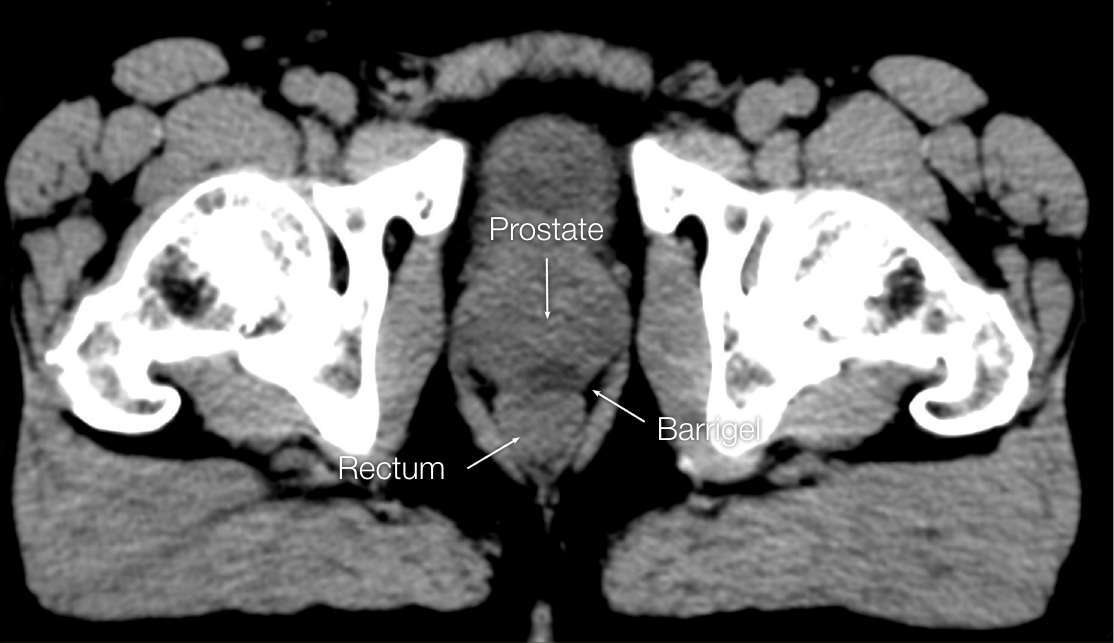

OPTIMIZING CT IMAGES

OPTIMIZING CT

IMAGES

Before (left) and after (right) adjusting window & level settings to enhance contrast and texture

CT images sourced from the Barrigel Pivotal Trial